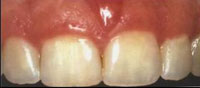

• Gingivitis: Early stage with inflammation and bleeding gums

Common Signs and Symptoms

Gum disease may not always cause pain in the early stages, which is why it can go unnoticed. Recognizing early signs can help in seeking timely treatment.

• Bleeding gums: Especially while brushing or flossing

• Swollen or red gums